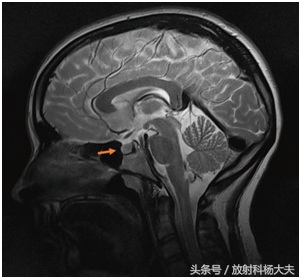

垂体瘤顾名思义来自垂体,那么首先我们看看这个罪魁祸首的老窝在哪里,上图是一个头颅侧面观(矢状位),箭头标注的位置就是垂体了,没错,就是这么一个垂在大脑下边的小东西,在茫茫的大脑中,它安静的偏居一隅,住在自己的安乐窝“垂体窝”内。这个住所看似僻静,实际上周围地形非常复杂。